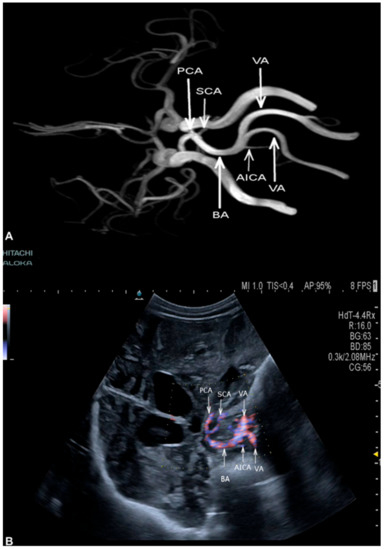

3.2. Cerebral Arteries